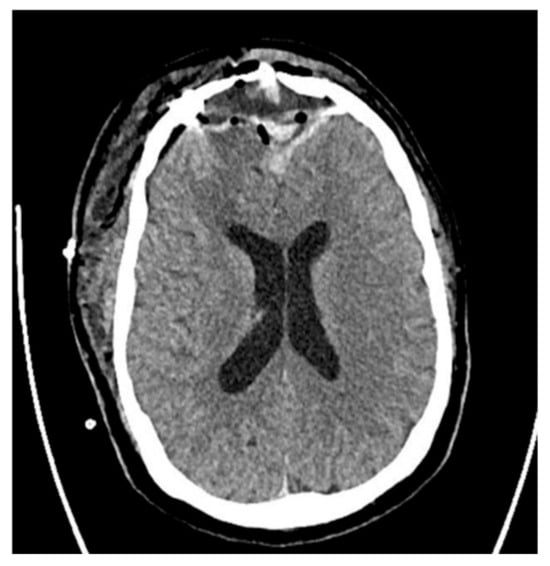

2. Case Presentation

5.5. Radiological Imaging